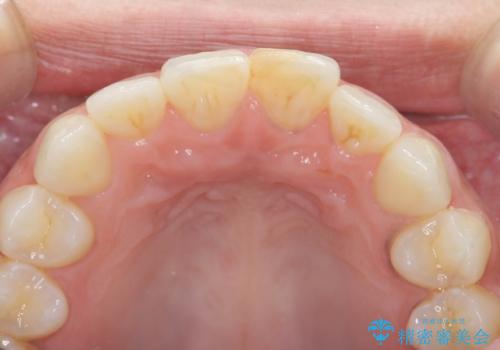

すり減った前歯の形態回復

- すり減ってしまった前歯の審美性の回復を希望され来院されました。

何度かレジン修復を試みたものの、脱離しやすく変色も気になる、とのことでセラミッククラウンによる審美性の回復を計画します。

右側は、クラウンにせず可及的に形態を整えることのみでの対応としました。

自然な色調のセラミッククラウンで審美性を回復することができ、大変満足いただけました。